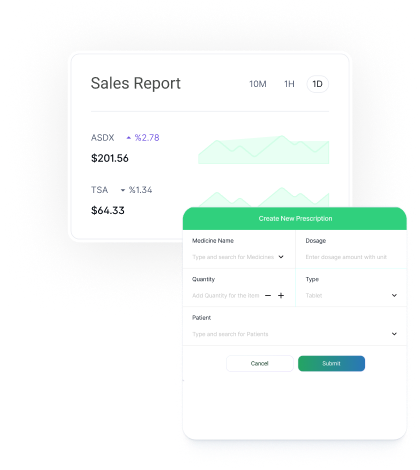

Generate and send prescriptions in seconds with just a few clicks. No handwriting errors, no misinterpretations—just clear, accurate digital scripts.Generate and send prescriptions in seconds with just a few clicks. No handwriting errors, no misinterpretations—just clear, accurate digital scripts.

Generate and send prescriptions in seconds with just a few clicks. No handwriting errors, no misinterpretations.

Complete audit trail and reporting system for all prescriptions issued by clinicians